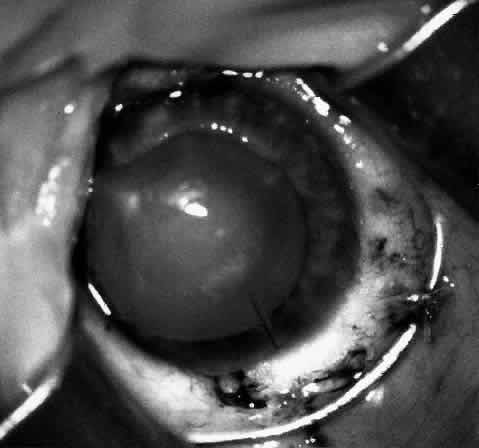

Sixteen to 22 interrupted 10-0 nylon sutures are placed to secure the edge of the lens in the peripheral corneal stroma trough. The first eight sutures are placed with the edge of the lens lying over the circular trephine mark (Fig. 10). As with any corneal transplant surgery, the second suture is the most important in centering the lens. All knots must be tied in such a way that the knots may be buried easily. At the same time, the sutures must not be tightened so tightly that compression occurs with the lens. My personal preference is for a 2-1-1 surgeon's knot. Care should be taken to prevent the lens from being sewn eccentrically into the bed, to prevent astigmatism. After the first eight sutures are placed, the edge of the lens is tucked into the stromal bed all around (Fig. 11) and the remaining 8 to 14 sutures are placed to fasten the lens securely in place (Fig. 12). The sutures are rotated so that the knots are buried in the recipient cornea. This allows the surgeon to remove the sutures at a subsequent examination under anesthesia (EUA) by means of traction directed peripherally without dehiscence of the wound.

Fig. 11. After the first eight sutures are in place, the edges of the lenticule are tucked into the bed.